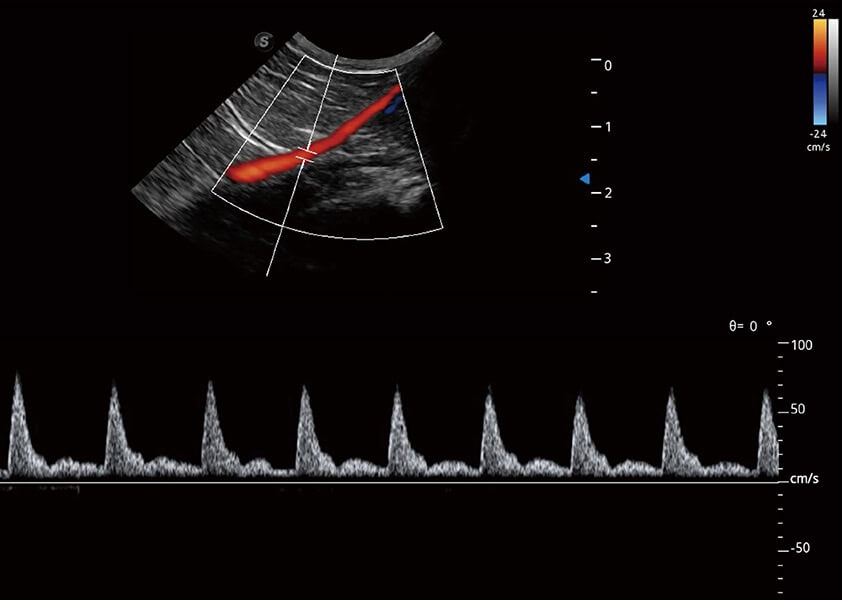

ProPet 60 作為一款高端臺(tái)式動(dòng)物超聲設(shè)備,為動(dòng)物醫(yī)生的日常診斷提供了一系列貼合動(dòng)物臨床需求、解決臨床實(shí)際問(wèn)題的高級(jí)成像功能。憑借全系列高清探頭,滿足醫(yī)生對(duì)腹部、心臟、生殖、淺表、肌骨等成像的所有需求,切實(shí)幫助您提升檢查效率,提高診斷信心。